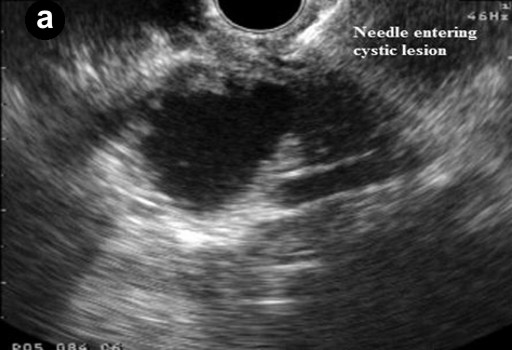

All patients had platelet count and coagulation profile checked and corrected if needed prior to the procedure. Procedures were done under intravenous sedation with diazepam and pethidine or midazolam and fentanyl. Cyst sampling was done by two operators with a combined experience of over 1,000 linear EUS procedures (GPA and KR). The lesion was identified and punctured using a 19 G needle using curvilinear echoendoscope (GF-UCT240-AL5, Olympus KeyMed, Essex, United Kingdom) and 50% of the cyst content was initially aspirated. The echobrush (Cook Medical, Limerick, Ireland, United Kingdom) was then passed through the handle and advanced through the needle till the whole brush could be visualised in the cyst. The wall of the cyst was then brushed by to and fro movement of the brush tip by moving the shaft of the needle at the handle. The opposite wall of the cyst was then visualised by moving the handle of the scope sideways and the brushing repeated at least four times (Figure 1). The brush was targeted if septae or nodules were present on the cyst wall. The brush was pulled back into the needle tip prior to removing the needle from the cyst and the needle apparatus with echobrush was withdrawn as a whole. The cyst was then aspirated to dryness using either a 19 G or 22 G needle. In patients where only FNA was done the cyst was punctured and aspirated using a 22 G needle.

Figure 1. Linear endoscopic ultrasound showing EUS-guided brushing of a cystic pancreatic lesion. a. EUS-FNA 19 G needle entering a cystic lesion in the head of the pancreas. b. The cyst being aspirated. c. The cyst wall being brushed by echobrush introduced through the needle. d. The cyst aspirated to dryness after cyst wall brushing. |